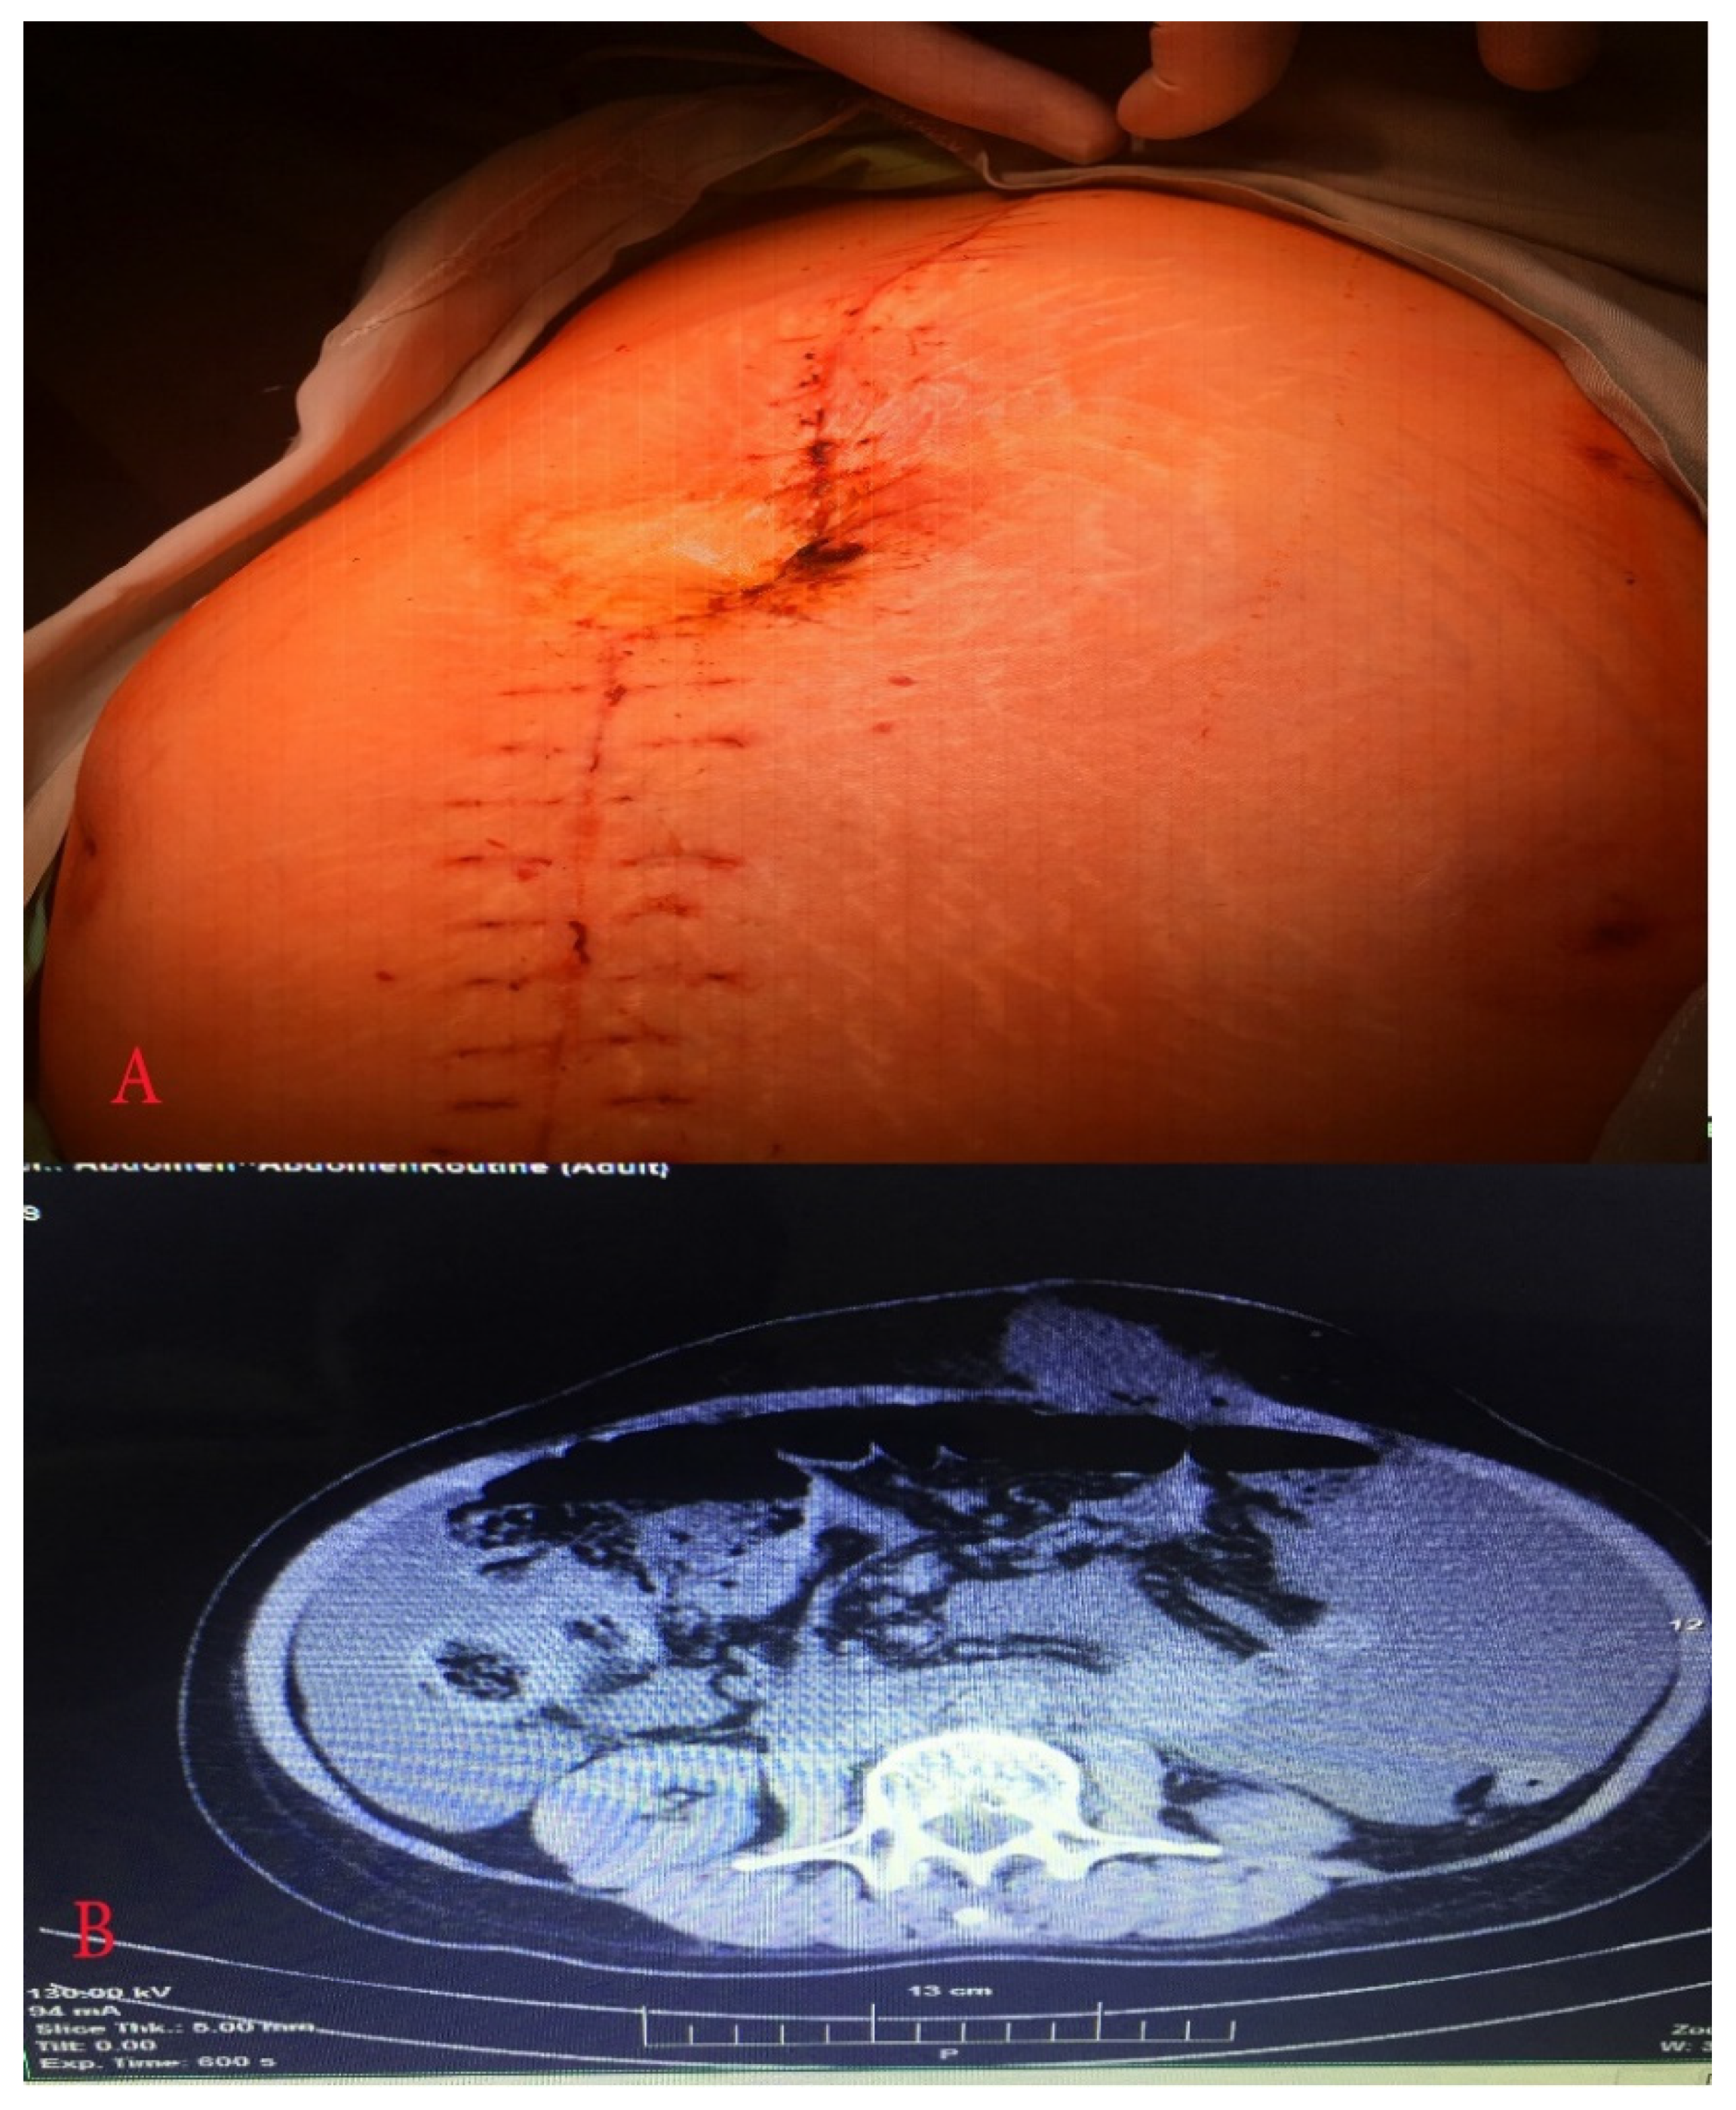

2. Case Report